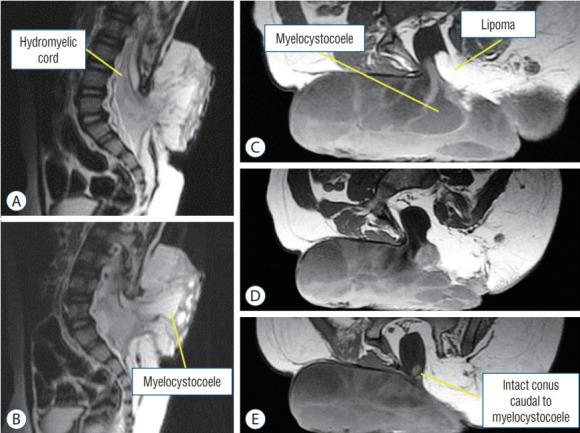

Spinal dysraphic lesions due to focal nondisjunction in primary neurulation are commonly encountered in paediatric neurosurgery, but the "fog-of-war" on these conditions was only gradually dispersed in the past 10 years by the works of the groups led by the senior author and Prof. Kyu-Chang Wang. It is now clear that limited dorsal myeloschisis and congenital spinal dermal sinus tract are conditions at the two ends of a spectrum; and mixed lesions of them with various configurations exist. This review article summarizes the current understanding of these conditions' embryogenetic mechanisms, pathological anatomy and clinical manifestations, and their management strategy and surgical techniques.

由于原发性神经管形成过程中的局灶性不分离导致的脊柱裂病变在小儿神经外科中很常见,但在过去10年中,由资深作者和王宇辰教授领导的团队的工作才逐渐驱散了这些病症上的“战争迷雾”。现在已经明确,有限性背侧脊髓裂和先天性脊柱皮样窦道是同一谱系两端的病症;并且存在各种形态的它们的混合病变。这篇综述文章总结了目前对这些病症的胚胎发生机制、病理解剖和临床表现,以及它们的治疗策略和手术技术的认识。